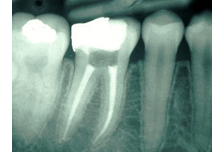

A root canal is a procedure done to save the damaged or dead pulp in the root canal of the tooth by cleaning out the diseased pulp and reshaping the canal. The canal is filled with a rubberlike substance to prevent recontamination of the tooth. The tooth is then permanently sealed, with possibly a post and/or a crown made of porcelain or metal alloy. This enables patients to keep the original tooth.

Once the dentist performs tests on the tooth and recommends therapy. Treatment usually involves one to three appointments. First, you will probably be given a local anesthetic to numb the area. A rubber sheet is then placed around the tooth to isolate it. Next, an opening is drilled from the crown into the pulp chamber, which, along with the root canal, is cleaned of all diseased pulp and reshaped. Medication may be inserted into the area to fight bacteria. Depending on the condition of the tooth, the crown may then be sealed temporarily to guard against recontamination, the tooth may be left open to drain or the dentist may go right ahead and fill the canals. If you're given a temporary filling, usually on the next visit it's removed and the pulp chamber and canal(s) are filled with material to prevent recontamination. If the tooth is still weak, a metal post may be inserted above the canal filling to reinforce the tooth. Once filled, the area is permanently sealed. Finally, a gold or porcelain crown is normally placed over the tooth to strengthen its structure and improve appearance.